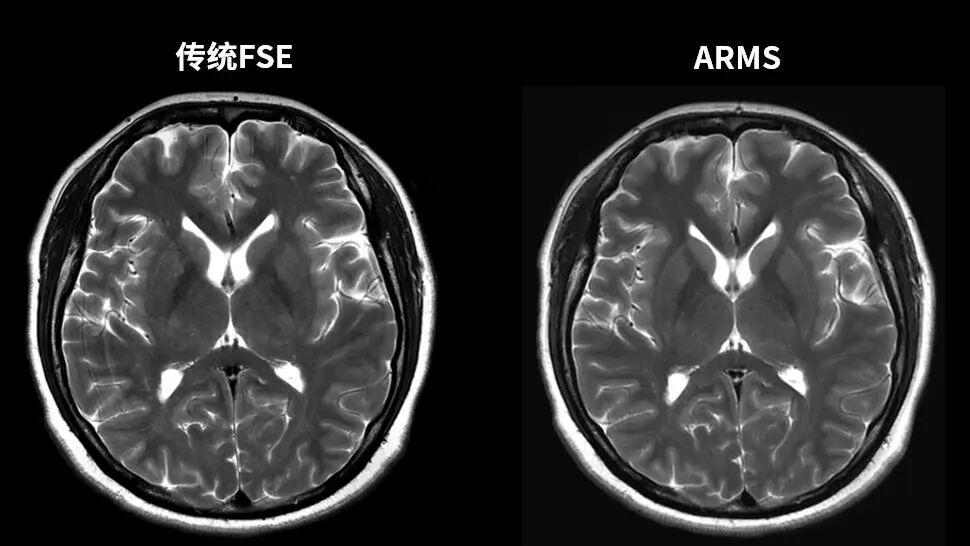

更高清

uMR870超高端3.0T科研型磁共振具备DeepRecon技术,在保证图像诊断细节的前提下,智能识别并去除噪声,突破了传统磁共振成像环节中图像信噪比和分辨率之间的矛盾。

02 智能深度重建   uAIFI DeepRecon™

智能深度重建,助力提升图像质量

基于卷积神经网络深度学习算法,引领场变,全身部位“高场强”成像。高信噪比、高分辨率、高保真、全身部位覆盖,相同扫描协议,大幅提升图像信噪比,提升诊断信心,助力高分辨成像,呈现更丰富解剖细节。